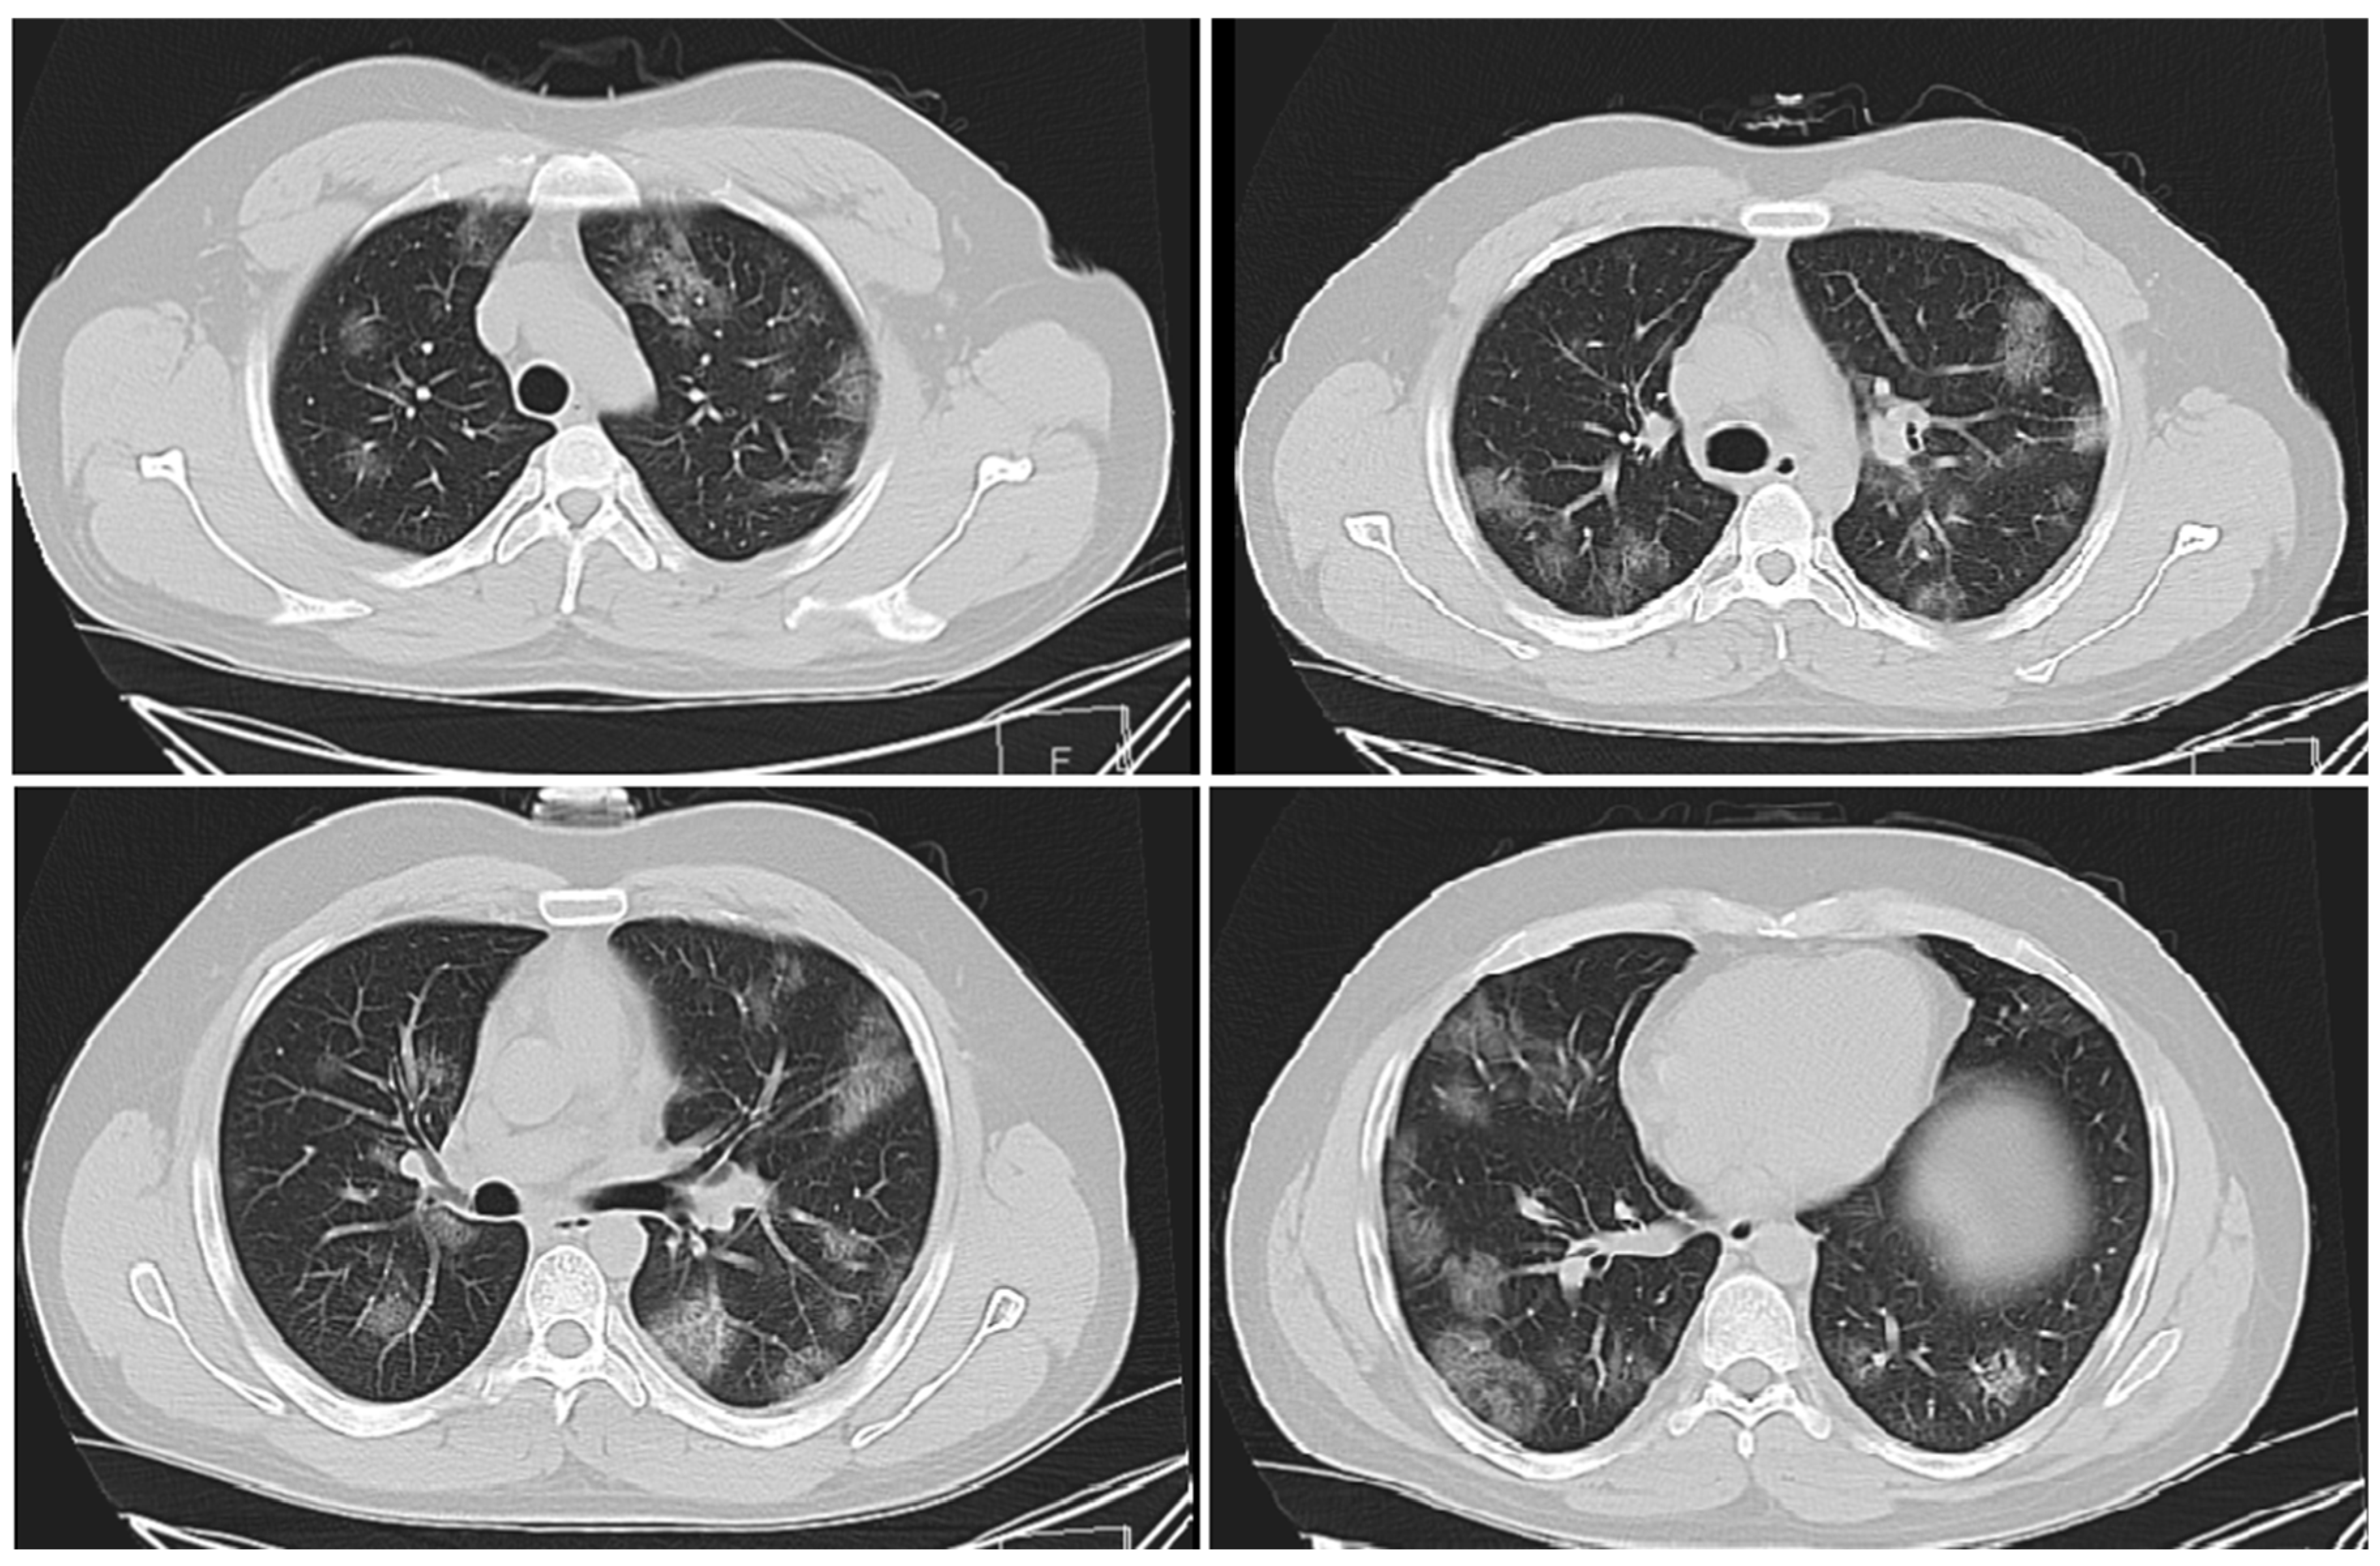

3.1.1. Cases Reports from Iran

Case 1

Case 2

Case 3

Case 4

Case 5